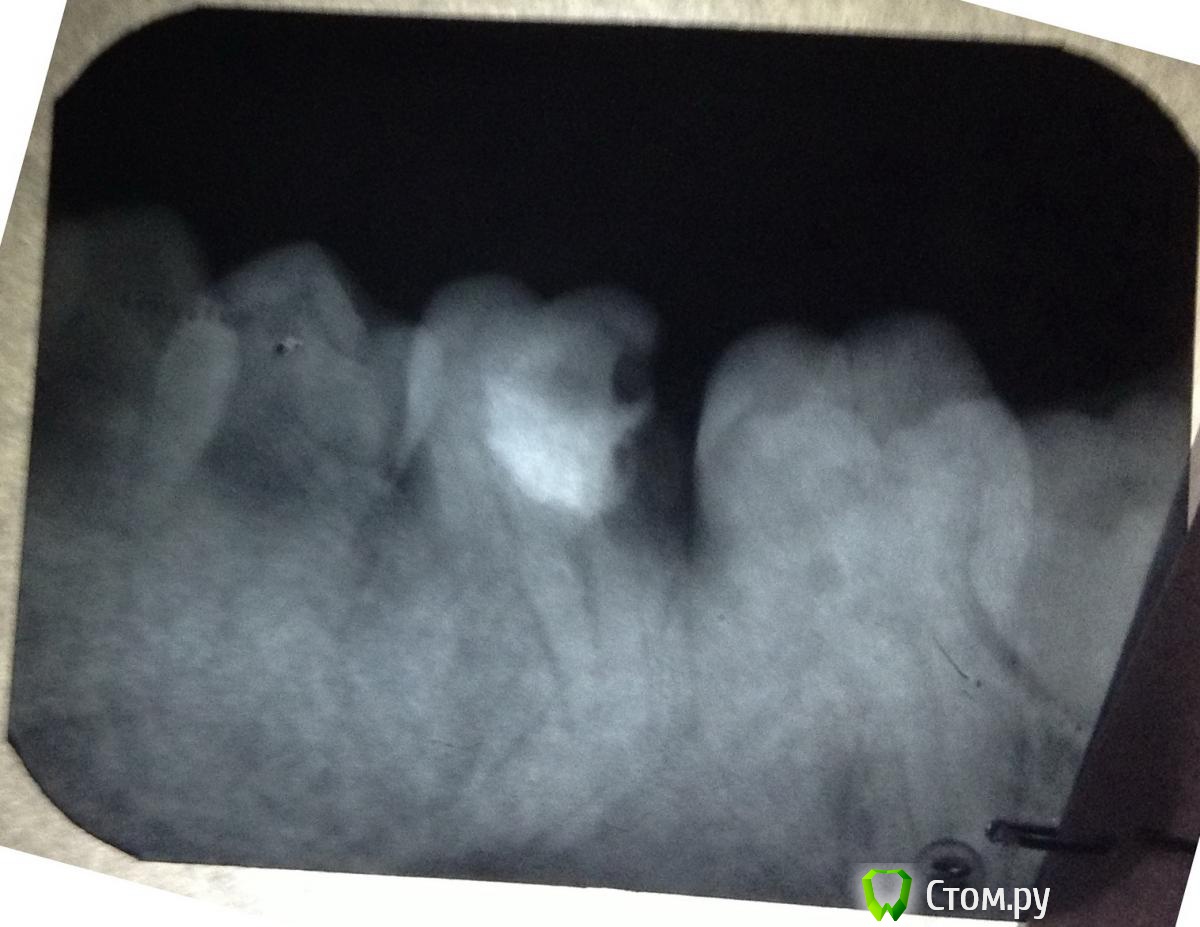

and13 Опубликовано 27 мая, 2014 Поделиться Опубликовано 27 мая, 2014 Приветствую. Ситуация такая: давно лечил зуб 36. Пломба и вроде каналы (не знаю точно насчет каналов, снимки прилагаю)Недавно откололось пломба, пошел к врачу. Она посмотрела снимки и сказала что тут ничего сделать нельзя совсем, зуб сгнил внутри якобы, только удаление зуба и ставить имплант. Направили к хирургу. Мне совсем не хочется удалять зуб. Вроде оставляют корни и ставят коронку или еще что? Посмотрите, выскажите свои предположения что можно сделать, жду любых советов. Спасибо п.с. качество фото может быть не очень, завтра могу приложить новые 1 Ссылка на комментарий

art700 Опубликовано 27 мая, 2014 Поделиться Опубликовано 27 мая, 2014 По снимкам зуб на удаление. А так снимки нужны получше Ссылка на комментарий

Scrabble Опубликовано 27 мая, 2014 Поделиться Опубликовано 27 мая, 2014 Дистально(сзади) зуб разрушен сильно-не восстановить. Ссылка на комментарий

and13 Опубликовано 27 мая, 2014 Автор Поделиться Опубликовано 27 мая, 2014 Сделал фото на фоне монитора. Вроде получше видно. П.с. делают же вроде коронку на штифт, чтобы не удалять зуб? Или может что-то еще подскажите?Корни то целые? Ссылка на комментарий

Scrabble Опубликовано 27 мая, 2014 Поделиться Опубликовано 27 мая, 2014 (изменено) Кариес корня. Дёсны кровоточат-сходите к гигиенисту, почистите, соблюдайте рекомендации по гигиене полости рта. Вылечите все зубы, нуждающиеся в лечении. Имплантация всё равно будет не сразу после удаления. На восьмой зуб обратите внимание-его тоже лучше удалить(причина-он ретинирован и расположен под углом к корню седьмого. Сам никогда полностью не прорежется-и может повлиять на состояние седьмого) Изменено 27 мая, 2014 пользователем Scrabble Ссылка на комментарий